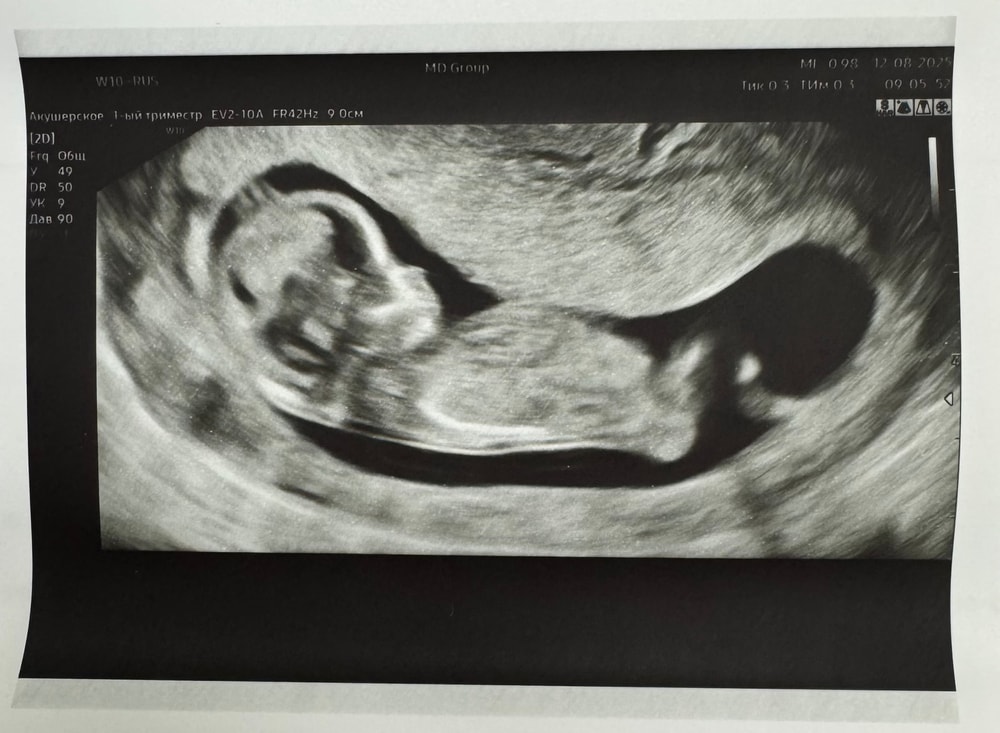

1ый криоперенос_1я беременность_1ый скрининг ✅

Мы прошли скрининг!

Все хорошо!! 🎉

Первую половину скрининга дочь активничала, крутилась, вертелась, а во вторую уснула, ее было не разбудить 😂

Написано 11 недель.

По сути это примерно 2.5 месяца.

Получается срок по переносу 12+3, хотя пишут они 12-13 недель.

Срок по КТР 12+6.

В целом, срок почти совпадает, разница в несколько дней. По КТР чуть опережаем)